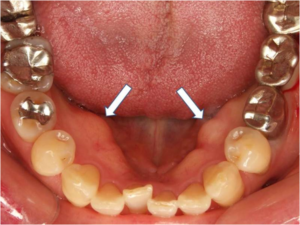

内側の歯ぐきにできたコブ(骨隆起)の有無

歯ぎしりによって強い力があごの骨に持続的にかかると、骨が反応して硬い盛り上がり、骨隆起が形成されることがあります。

骨隆起は主に下顎の内側や上顎の口蓋部に現れ、舌で触れるとコブのように感じられます。

形成はゆっくり進むため、初期段階では気づきにくいことがありますが、舌で口の内側を触って、以前にはなかった硬い盛り上がりを感じた場合は、歯科医院で確認してもらうようにしましょう。